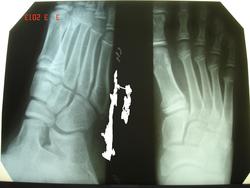

Мальчик, 11 лет. Обращение в травмпункт с жалобами на боли в правой стопе. Упал на горке. «Мозговым штурмом» этот случай назвать будет слишком громко. Так, легкая разминка перед тренировкой. Прошу извинить за качество снимков, но патологию (в общем и целом) видно.

Перелом основания I плюсневой. Нечасто встретишь...

перелом основания 1 плюсневой кости по типу остеоэпифизеолиза, в травмпункте у детей встречается не редко, раз в неделю точно есть))) остальное здесь - возрастная норма

Перелом основания 1 плюсневой кости скорее является застарелым. Формирование ложного сустава? Является ли он причиной болей применительно к свежей травме?

Братцы, да вы что! Какой застарелый? Какой ложный сустав?.. Да и остеоэпифизеолизом я бы не рискнула его назвать

Вот уж не предполагал, что по этому случаю дискуссия будет столь оживленной! Перелом не застарелый, обращение в травмпункт на следующий день после травмы. Ложным суставом, разумеется, и не "пахнет". А насколько принципиально, остеоэпифизеолиз это или "обычный" перелом? Тактика, в общем-то, одна и та же, и сроки сращения одинаковые.

В данном случае имеется деформация кортекса и нарушение балочной структуры прилежащей к зоне роста внутреннего сектора метадиафизарной зоны, по типу "сминания" кости. Высока вероятность того, что перелом вхож в ростковую зону, медиальный сектор ее шире, нежели остальная часть физарной линии. Скорее всего, повреждение её здесь есть, частичное. Наблюдать в динамике рост кости обязательно, хотя, думаю, принципиального влияния на форму и длину кости данная травма не окажет.

Что же касается обсуждаемого случая - на мой взгляд, зону роста он совсем не затрагивает, имеет место сминание кости по типу "зелёной ветки".